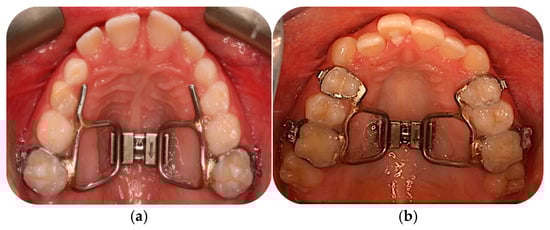

2.3. Orthodontic Treatment with RPE for Group A

Appendix A.1. Orthodontic Treatment with RPE for Group A